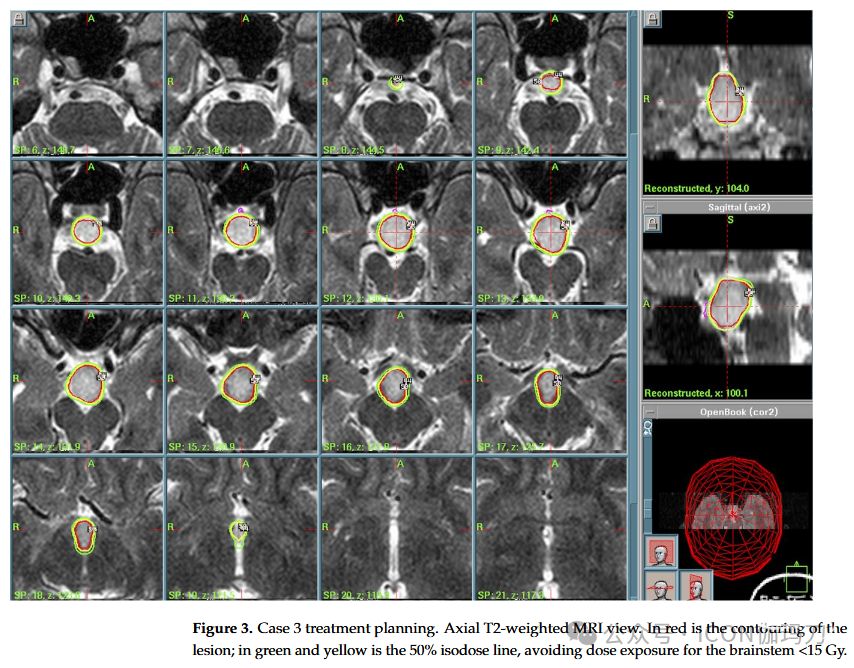

病例3:一名29岁男性,长期出现部分复杂和痴笑性癫痫发作,精神状态改变,危重期具有侵袭性。MRI显示下丘脑无强化病变占据第三脑室和乳头体的底部。在采取观望方法后,后续MRI显示下丘脑病变缓慢且进行性增长,也累及鞍区至视交叉。癫痫发作出现耐药性,因此建议采用GKR 治疗(PI为50%,PD为13 Gy, MD为26 Gy,总剂量51.2 mJ, 12 Gy体积4.18 cc)代替手术(由于患者拒绝并经过多学科评估)并实施(2009)。(图3)患者放射外科治疗后出院,无神经功能障碍。临床和影像学随访显示肿瘤生长控制良好(2019年8月),患者未出现视野缺损或激素损伤。过去的神经学评估(2019年8月)报告了2种抗癫痫药物(左乙拉西坦和丙戊酸[Levitiracetam and Valproate])对癫痫发作的良好控制。

图3。病例3治疗方案。轴位T2加权MRI视图。红色是病变的轮廓;绿色和黄色为50%等剂量线,避免脑干<15 Gy的剂量暴露。